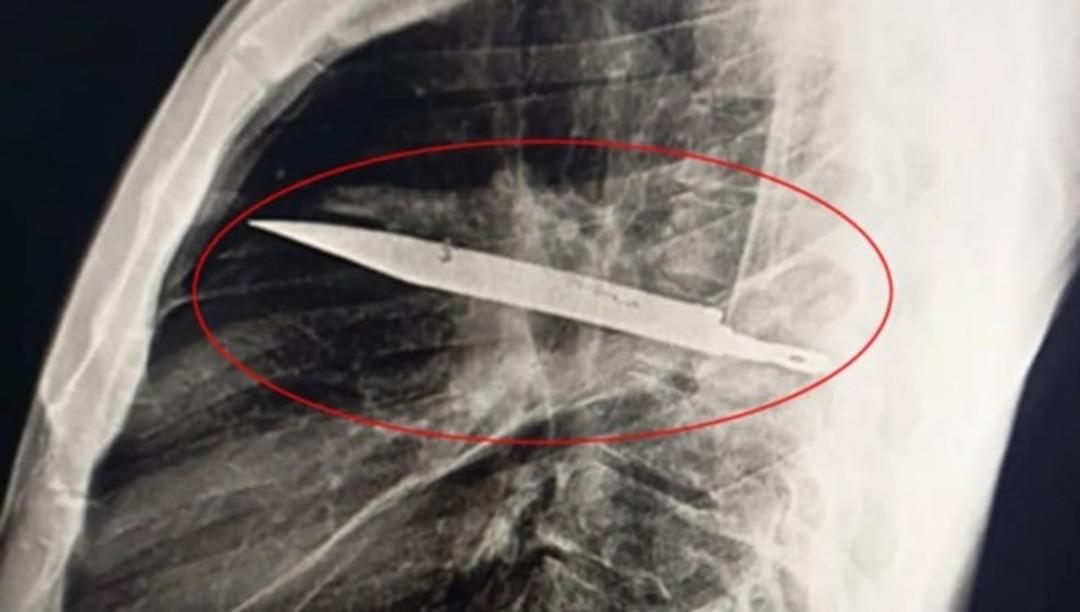

Tanzanya’da bir adam, göğüs ağrısı ve irin gelmesi şikayetiyle hastaneye başvurduğunda, tam sekiz yıldır göğsünde büyük bir bıçak parçasıyla yaşadığı ortaya çıktı.

44 yaşındaki hasta, sağ memesinden 10 gündür beyaz irin geldiğini belirtti. Çekilen röntgende, göğsünün içinde büyük bir bıçak tespit edildi. sekiz yıl önce kavga sırasında yüzünden, sırtından ve göğsünden yaralandığını, o dönemde hastanede sadece dikiş atıldığını hatırladığını söyledi. Ancak o dönemde bulunduğu hastanede görüntüleme imkanı olmadığı için vücudunda yabancı cisim fark edilmedi.